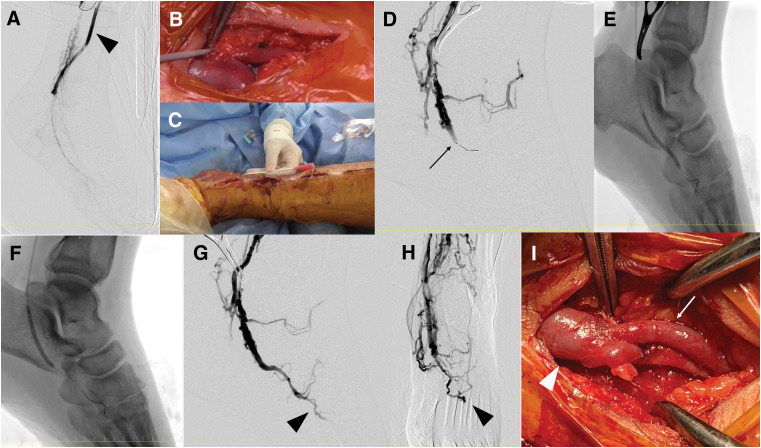

Case presentation: A 51-year-old man with a 12-year history of TAO presented with rest pain and a necrotic ulcer on the 2nd toe. He had recently ceased smoking after a 31-year history. Imaging demonstrated complete occlusion of the popliteal and tibial arteries, with foot perfusion reliant on corkscrew collaterals. The ankle-brachial index was 0.43, and skin perfusion pressure (SPP) was critically low. A severely diseased plantar artery was identified as a potential distal target. Given the high risk of graft failure, a hybrid strategy combining in situ bypass and surgical distal venous arterialization (DVA) was preoperatively planned. To mitigate perioperative vasospasm, a lumbar sympathetic block was administered 1 week prior to surgery. An in situ bypass using the ipsilateral great saphenous vein was constructed from the superficial femoral artery to the plantar artery. DVA was established via retrograde puncture of the plantar vein, balloon angioplasty for valve sites, and end-to-side anastomosis to the bypass graft. Early duplex ultrasonography revealed anastomotic stenosis at the DVA site as well as stenosis at valve sites, both of which were successfully managed with a single endovascular procedure. The toe stump healed completely within 3 months. The graft remained patent for 2 years, and SPP was preserved even after graft occlusion. Notably, graft failure coincided with DVA occlusion, suggesting its critical role in maintaining flow. At 42 months postoperatively, the patient remained ulcer-free with favorable perfusion, pain-free ambulation, and full return to work.